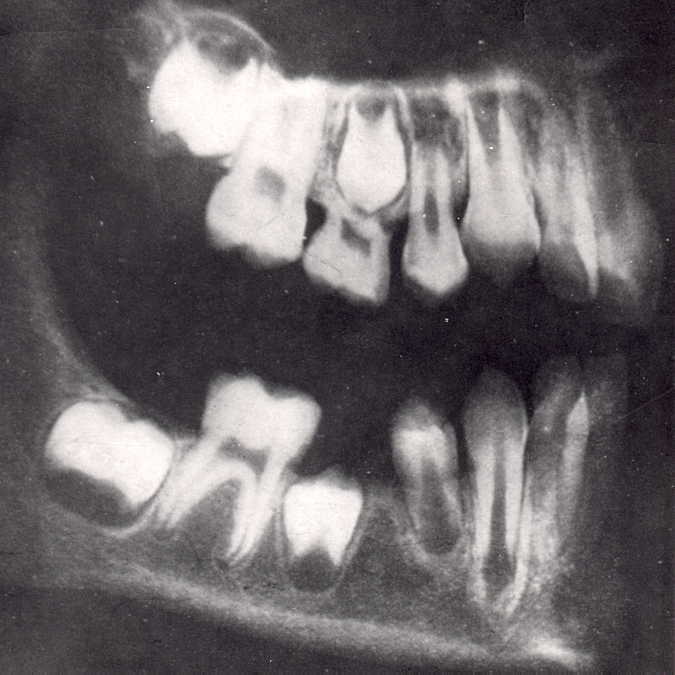

X-quang hàm trên và dưới trẻ sơ sinh | ![]()